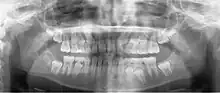

Radiografia panorâmica

A radiografia panorâmica (também chamada de pan tomografia ou ortopantomografia) é uma técnica que produz uma única imagem tomográfica das estruturas faciais que inclui ambos os arcos dentários, maxilar e mandibular, e suas estruturas de suporte. Essa é uma variante curvilínea da tomografia convencional e também se baseia no princípio de movimento recíproco da fonte de raios X e de um receptor da imagem ao redor de um plano ou ponto central, denominado plano de corte, no qual se localiza o objeto de interesse. Objetos em frente ou atrás desse plano de corte não são visibilizados de forma clara em virtude do seu movimento em relação ao centro de rotação do receptor e da fonte de raios X.

A radiografia panorâmica é um importante exame radiográfico utilizado para o diagnóstico e planejamento terapêutico das doenças dos pacientes e ossos da face. É uma das técnicas radiográficas mais solicitadas e difundidas em todas as especialidades da Odontologia, onde a visualização de todos os elementos dentais e suas estruturas anatômicas são de fácil compreensão para o dentista. O critério para a seleção de um exame radiográfico deve obter o equilíbrio entre o melhor diagnóstico e a menor dose de radiação admissível[1]. As principais vantagens das radiografias panorâmicas incluem as seguintes:

Radiografias panorâmicas são mais úteis clinicamente para o diagnóstico de problemas que requerem ampla visualização dos maxilares. Exemplos comuns incluem avaliação de traumatismo, localização de terceiros molares, patologias extensas, lesões grandes conhecidas ou suspeitadas, desenvolvimento dentário (em especial na dentição mista), retenção de dentes ou ápices radiculares (em pacientes edêntulos) e anomalias de desenvolvimento. Essas funções não requerem a alta definição e o alto detalhe das radiografias intra-orais. As radiografias panorâmicas são comumente usadas como a imagem inicial de uma avaliação por permitir adequada visualização ou auxiliar na indicação de outras radiografias. As radiografias panorâmicas também são úteis em pacientes que não têm boa tolerância a exames intraorais. No entanto, quando um exame radiográfico intraoral completo é realizado em um paciente que será submetido a tratamento dentário, normalmente pouca ou nenhuma informação útil adicional é obtida através de uma radiografia panorâmica simultânea.

A principal desvantagem da radiografia panorâmica é que as imagens não apresentam um detalhe das estruturas anatômicas tão bom quanto o das radiografias periapicais intra-orais. Portanto, as radiografias panorâmicas não são tão úteis quanto radiografias periapicais para a detecção de pequenas lesões cariosas, detalhes das estruturas periodontais ou doença periapical. As superfícies proximais de pré-molares também normalmente se sobrepõem. Logo, a disponibilidade da radiografia panorâmica em um paciente adulto comumente não exclui a necessidade de radiografias intra-orais para o diagnóstico das patologias odontológicas mais comumente encontradas. Outros problemas associados à radiografia panorâmica incluem ampliação desigual e distorção geométrica ao longo da imagem. Ocasionalmente, a presença de estruturas sobrepostas, como a coluna cervical, pode mascarar lesões odontogênicas, particularmente na região de incisivos. Além disso, objetos clinicamente importantes podem estar situados fora do plano focal (plano de corte) e podem aparecer distorcidos ou não aparecer.